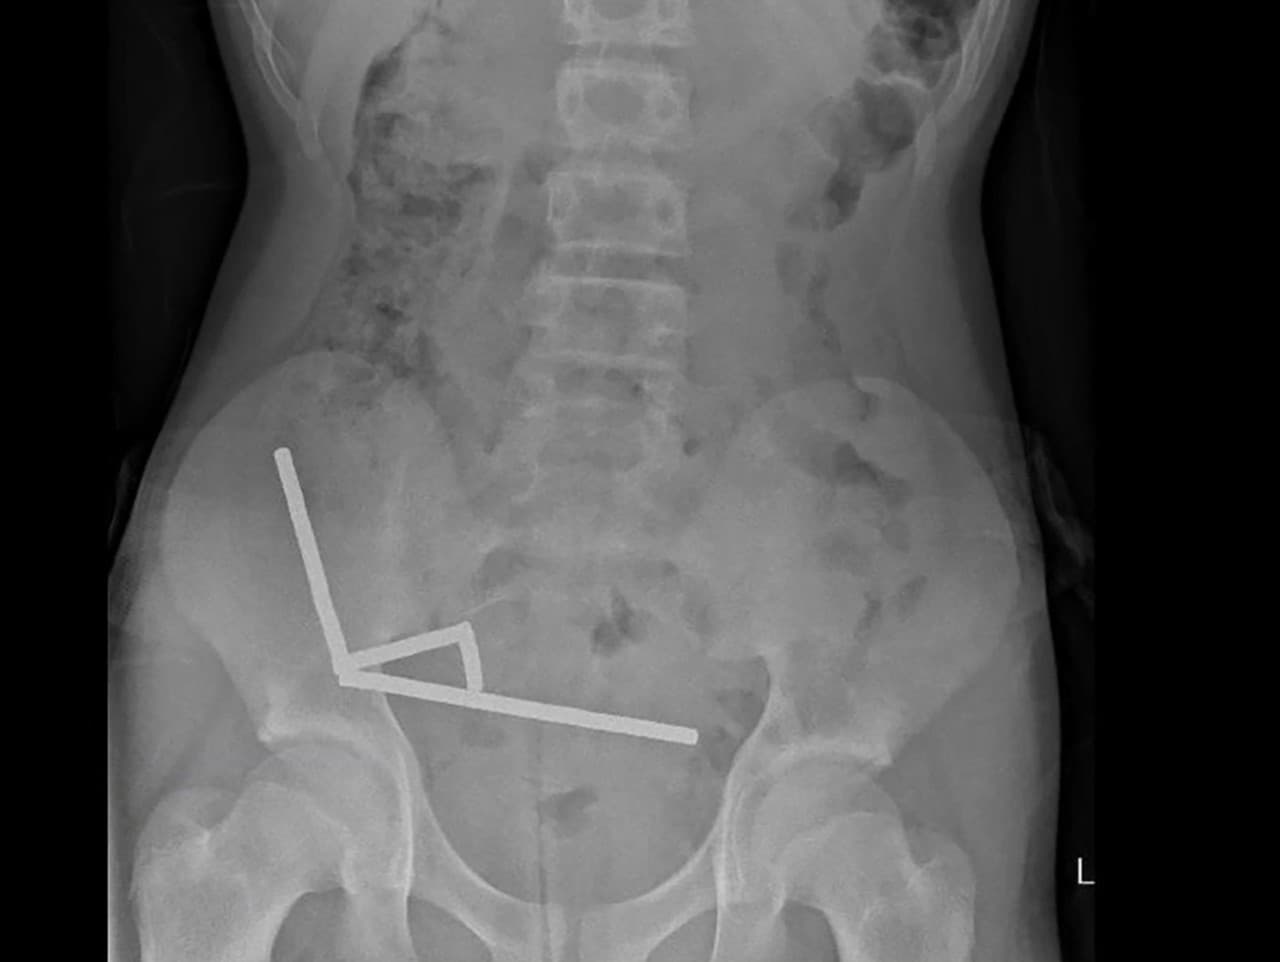

Röntgenové snímky odhalili desivý obraz – magnety sa v jeho tráviacom trakte usporiadali do štyroch dlhých reťazcov, ktoré sa v rôznych častiach čriev priťahovali a lepili k sebe. Lekári uviedli, že magnetické sily pritiahli slučky čreva tak tesne, až vznikla nekróza, teda odumretie tkaniva. Poškodené boli štyri úseky tenkého čreva aj slepé črevo.